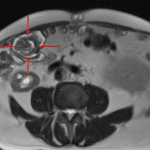

- Left lower quadrant transplant kidney with moderate hydroureteronephrosis and a ureteral stent in place

- Bilateral native renal atrophy with numerous bilateral renal structures of varying size and attenuation

Left lower quadrant transplant kidney with moderate hydroureteronephrosis and a ureteral stent in place.

Multiple structures of varying size and attenuation in both native kidneys, which likely represent cysts of varying complexity. Recommend nonemergent renal ultrasound for further evaluation if not previously performed.